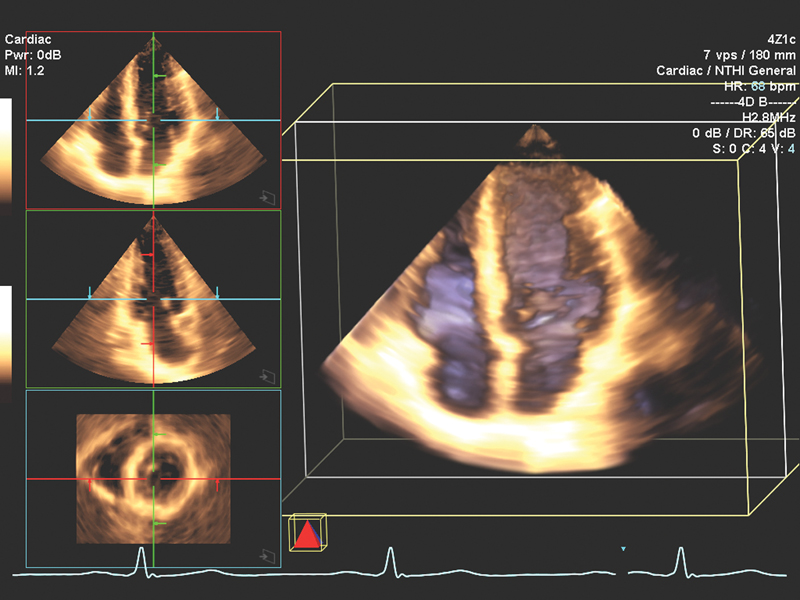

فحوصات تشخيصية لبعض امراض القلب والشرايين التاجية